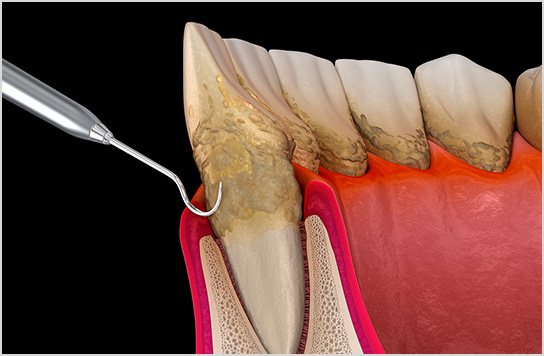

歯科用顕微鏡を利用すること

で、外科処置なしで

治療が可能。また外科を行わ

ない再生療法にも対応。

■歯周病の再生療法

歯周病が原因であごの骨が溶けてしまい歯がグラグラしていたケース。

再生療法で骨を再生させ抜歯せずに治療できた。